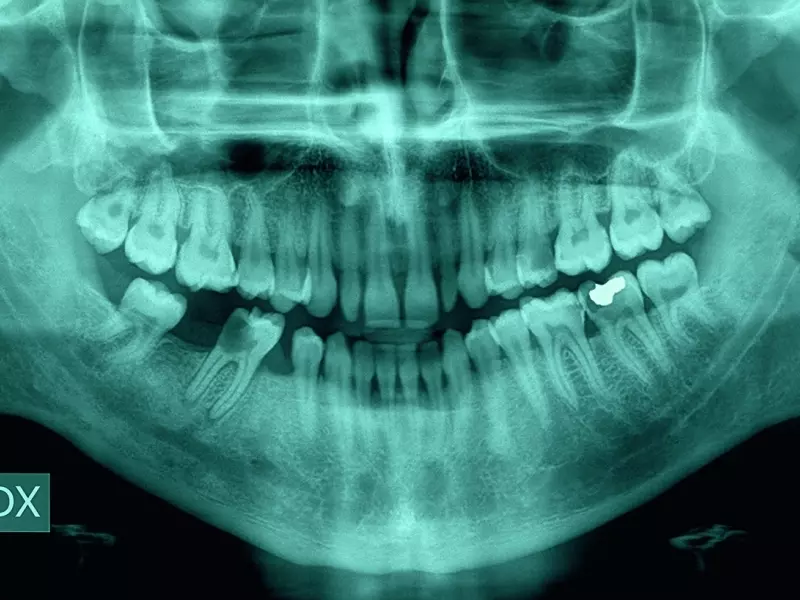

Endodoncja nie musi być trudna - rozwiązania problemów z boczną kondensacją zimnej gutaperki